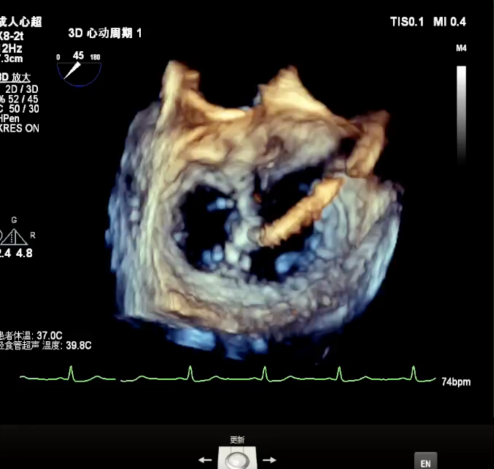

3D enface view示二尖瓣P2P3区瓣叶脱垂,偏心性返流

3D测量二尖瓣瓣口面积4.50cm² 病变宽度为1.79cm

3D指示下调整瓣膜夹朝向病变区域P2偏P3区

确定瓣膜夹与病变区域垂直后,放下夹片,超声确认前叶后叶都夹合充分,3D检查瓣膜夹位置.